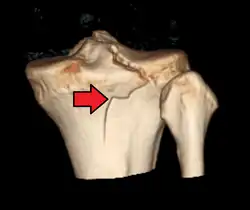

3D reconstruction of a CT image of a tibial plateau fracture -